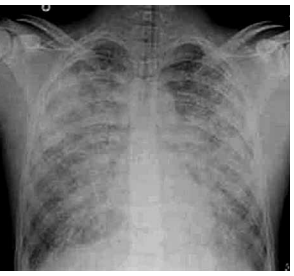

Exame de imagem:

(Disponível em: https://resources.wfsahq.org/ atotw/sindrome-do-desconforto-respiratorio-agudo/)